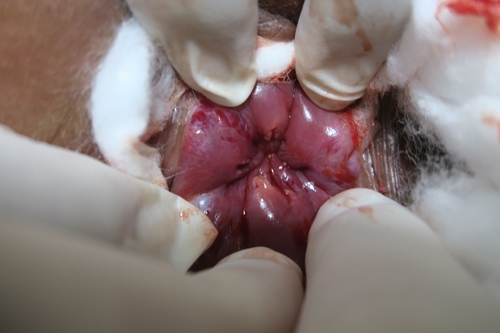

ฝีคันฑสูตร

ฝีบริเวณใกล้เคียงทวารหนัก

ฝีคันฑสูตร/ฝีรูปลาไหล